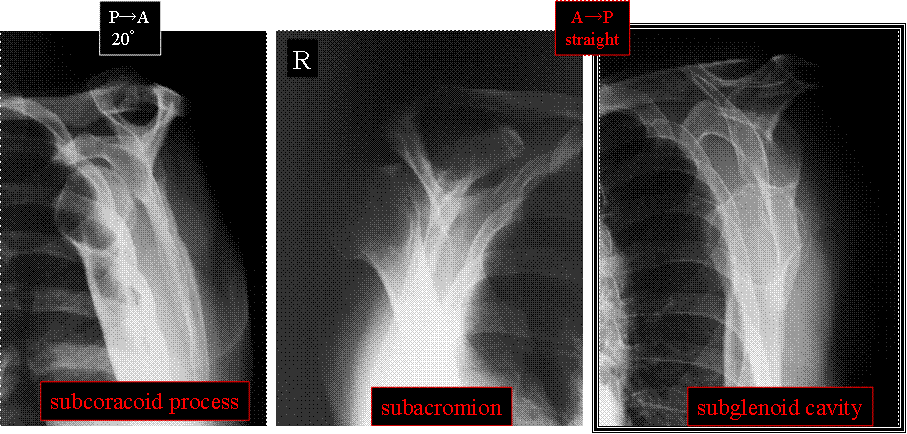

X線straight水平入射 座位立位AP撮影法 仰臥位AP撮影法 “肩部Yview画像”基準PA撮影法

座位で患者さんに優しい撮影法